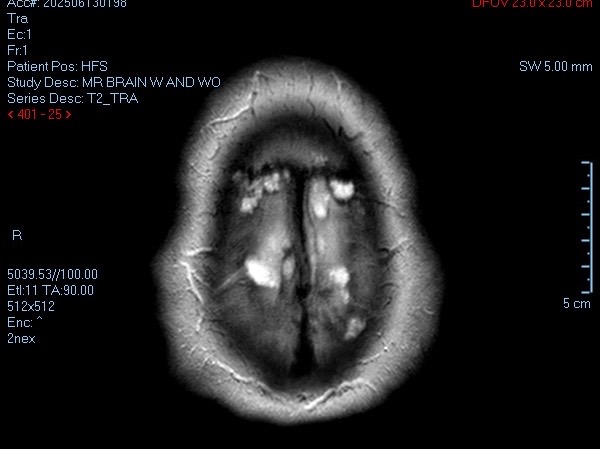

Hi. My name is Scott McDaniel. I was diagnosed with MS (multiple sclerosis) in July of 2025 after becoming ill in November of 2023. As of December 2025, my doctors are now leaning toward additional central nervous system, immune system and neurological diseases along with discovery in my MRIs of at least 2 strokes during my illness.

- My biggest fear right now is that the advanced hypertension and other medical issues are going to cause another stroke and I will not be able to communicate or move. The idea of being trapped in my own mind terrifies me beyond comprehension.